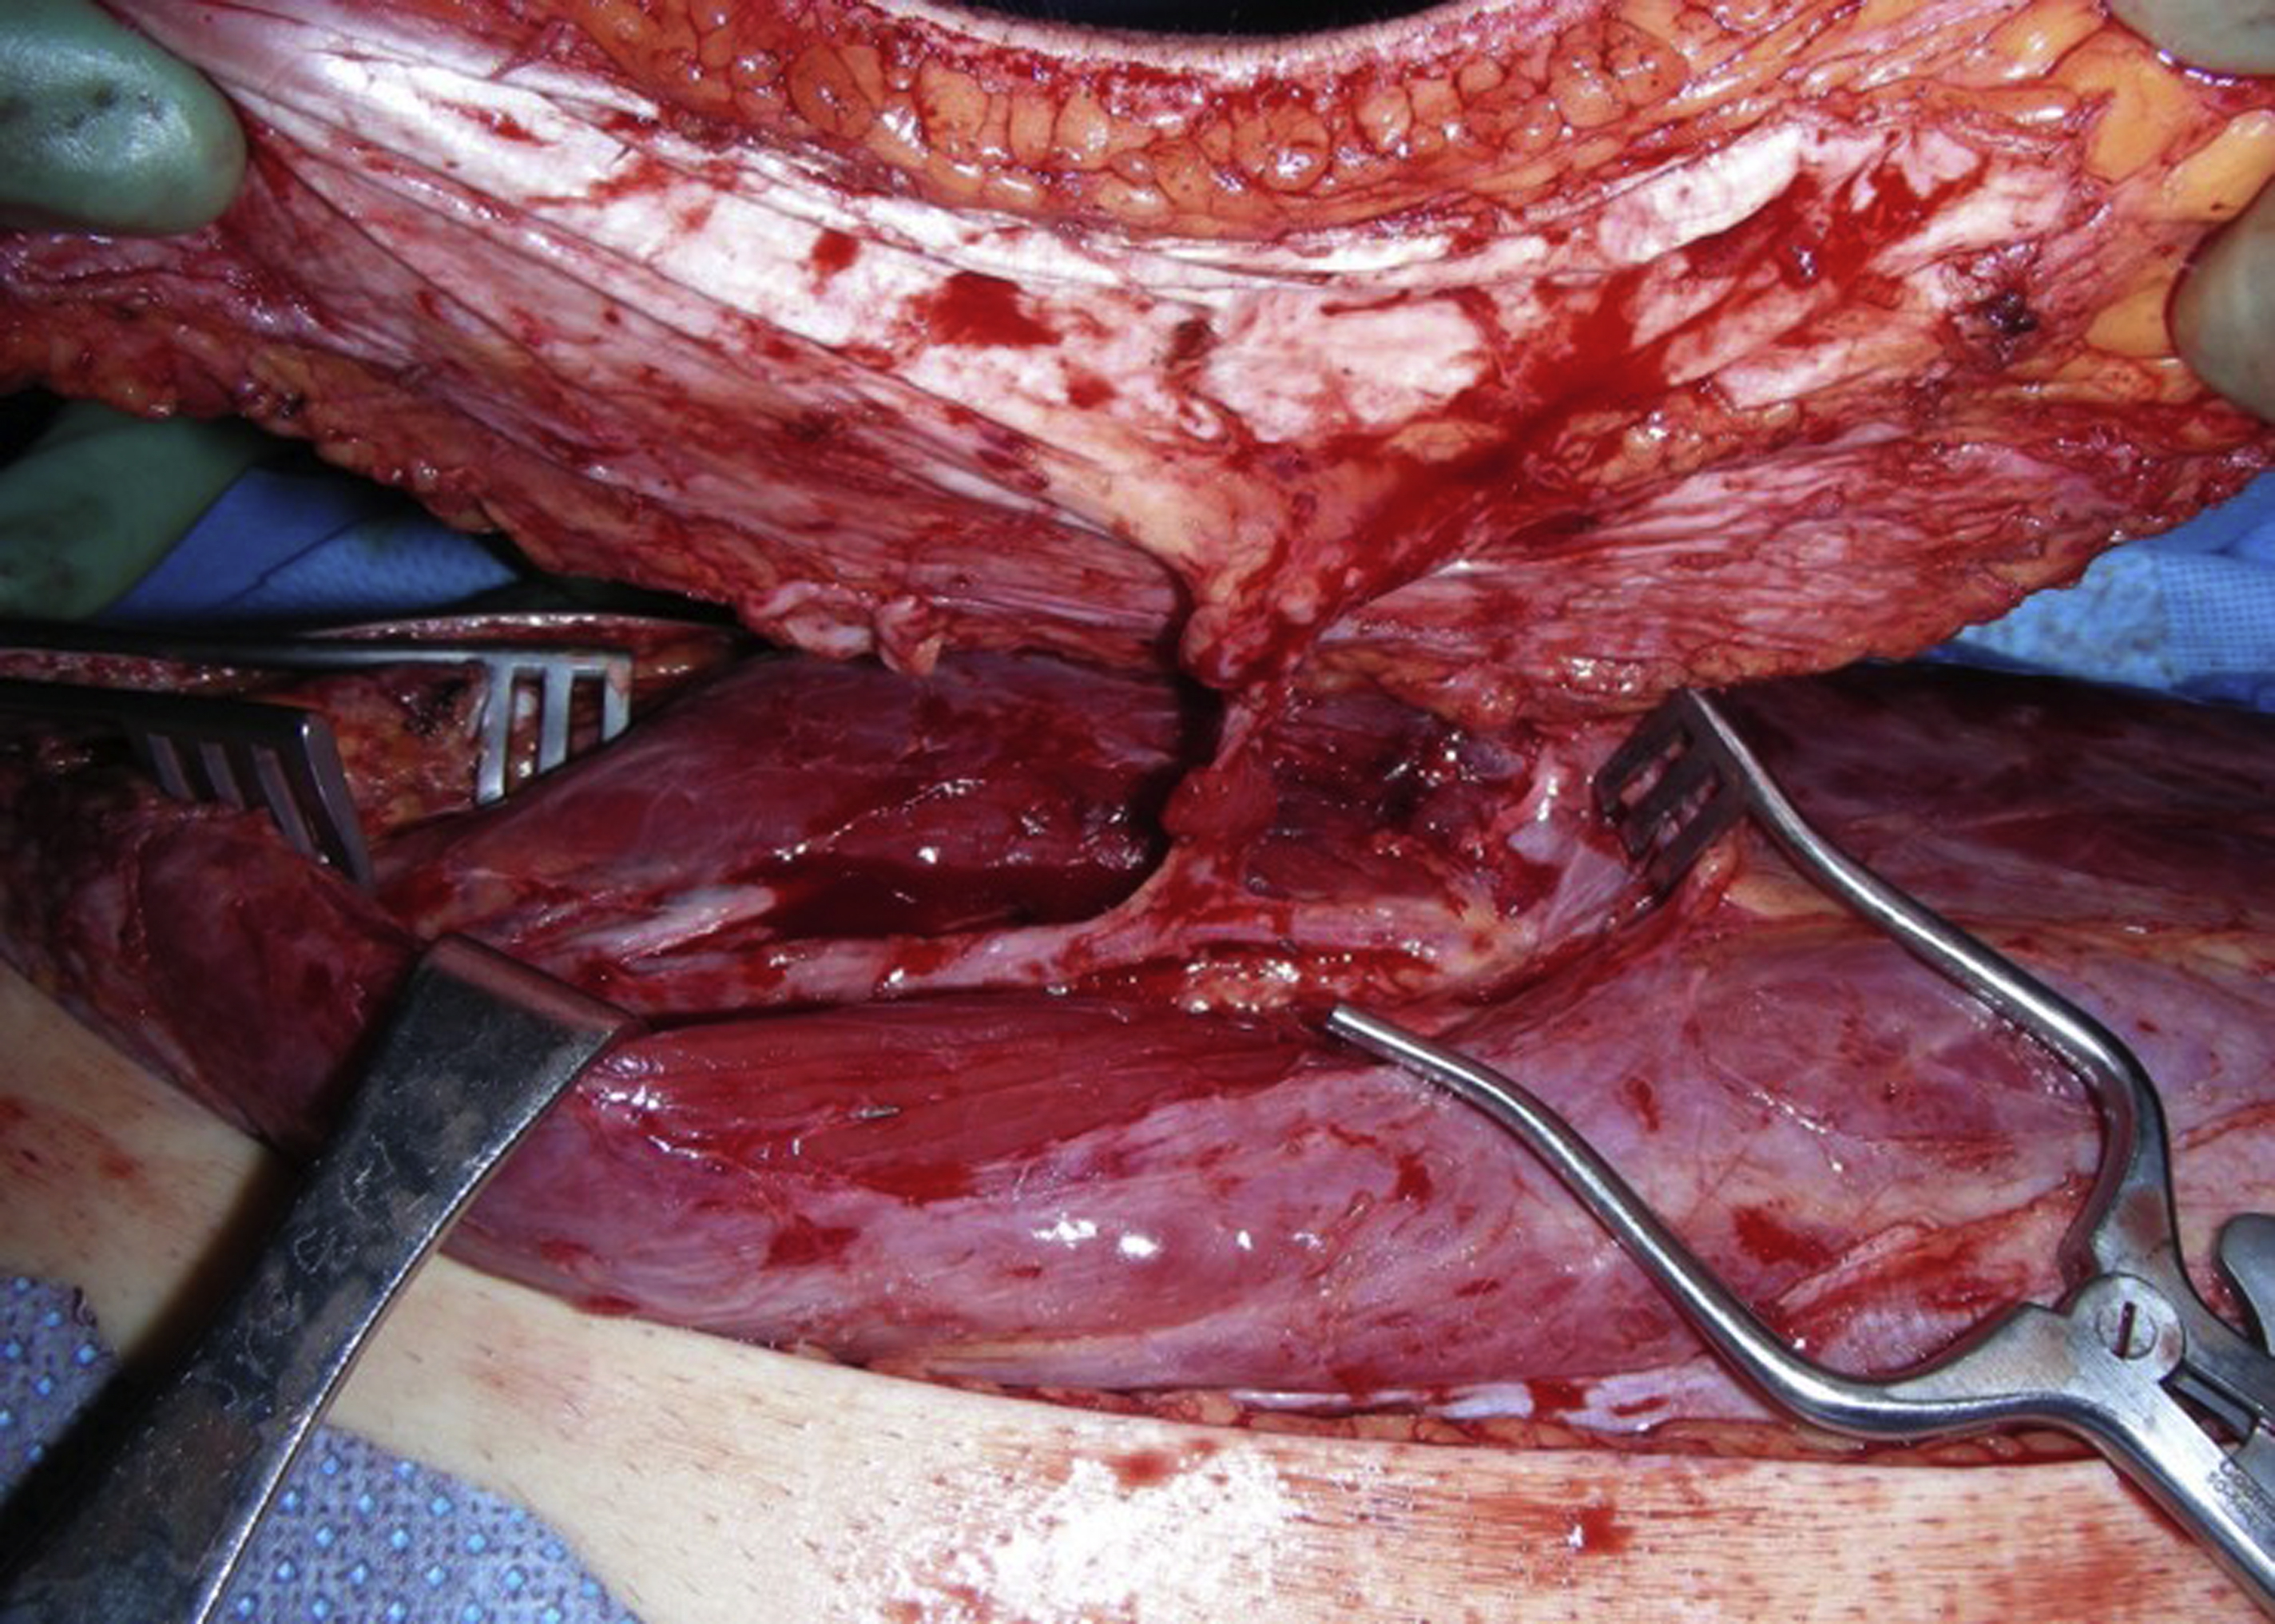

Flap Dissection

To ensure a relatively quick and easy flap dissection, the surgeon should know as much as possible about the detailed vascular anatomy of the flap before its dissection. This is particularly true for most perforator flaps. In the author’s practice, a duplex scan is routinely used for the preoperative mapping of the perforators, as well as the pedicle of the perforator flap before the flap dissection. In this way, the size and the number of the perforators that can be selected for the flap, the course of potential intramuscular dissection, and even the depth of the flap’s pedicle are evaluated. With this critical information in mind, a perforator flap, such as an ALT flap, can be elevated smoothly and safely. For an ALT flap dissection, the combination of retrograde and antegrade dissections of the pedicle can be performed for an easy flap dissection once the skin paddle of the flap is elevated ( Fig. 2 ).